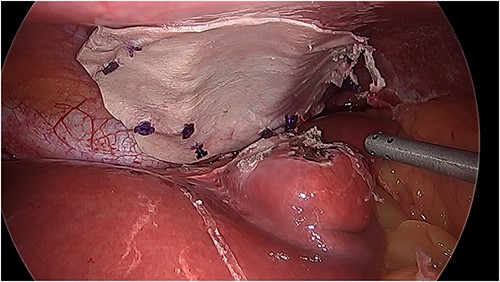

There was an obvious 2 × 2 cm defect in the diaphragm allowing for communication with the pericardial sac. The inferior aspect of the heart was visible through this defect (Fig. 3). Bovine pericardial tissue was glued using Glubran 2® and Absorbatak® to the inferior aspect of the diaphragm to cover the defect. Glubran 2® was applied intermittently around the circumference of the patch, preventing a complete seal from being created and continuing to allow excess pericardial fluid to drain into the peritoneal space (Fig. 4).

Intraoperative photo demonstrating the defect in the central tendon of the diaphragm into the pericardium after the liver had been reduced. The liver appeared viable on inspection.

Intraoperative photo of the repair with bovine pericardial tissue.